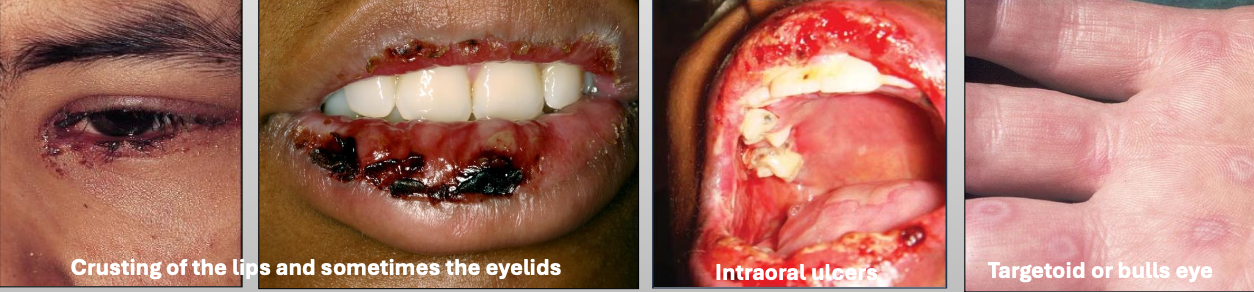

What are characteristics of Stevens-Johnson Syndrome?

Almost Always triggered by drugs (medication)

<10% of body surface is affected

Younger

Initially on trunk

Sever sloughing of skin

What are characteristics of Toxic Epidermal Necrolysis (Lyell disease)?

Almost Always triggered by drugs (medication)

≥30% body surface is affected

Older females

Initially on trunk

Sever sloughing of skin